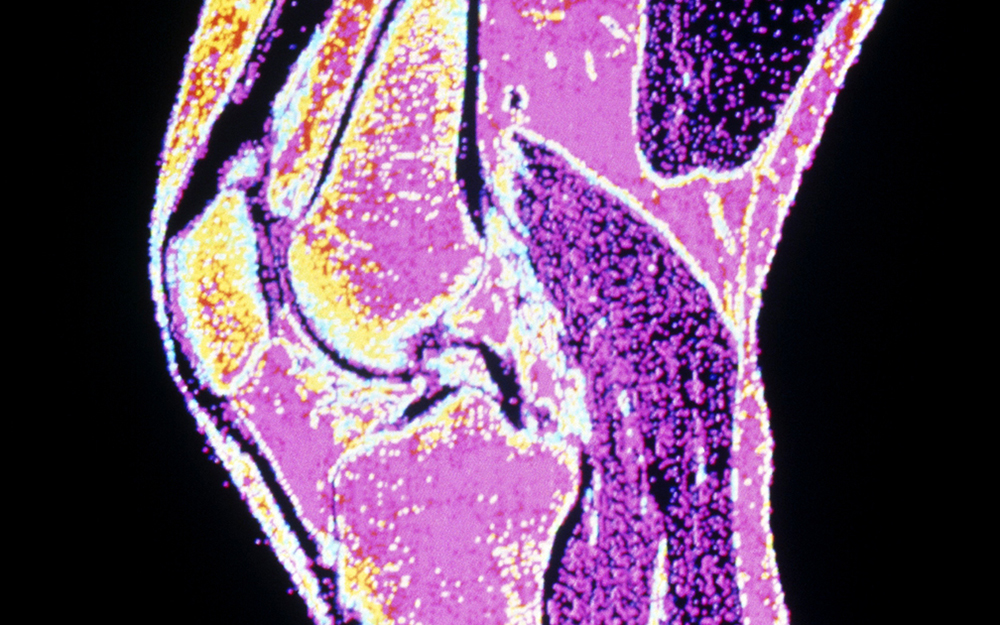

You may have torn your anterior cruciate ligament (ACL), the stabilizing ligament in your knee that connects your thighbone to your shinbone.